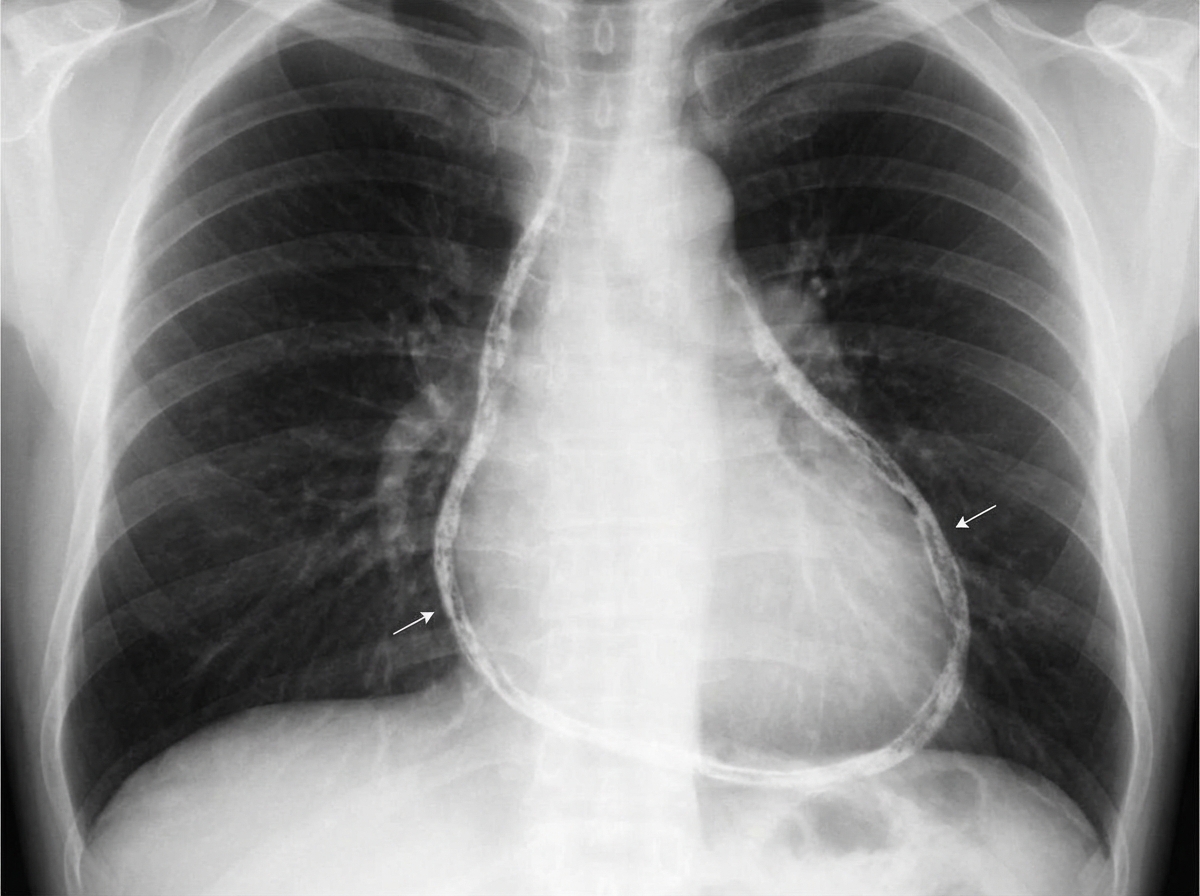

A 75-year-old over-weight gentleman with a long history of uncontrolled hypertension, diabetes, smoking and obesity is presenting to his primary care physician with a chief complaint of increased difficulty climbing stairs and the need to sleep propped up by an increasing number of pillows at night. On physical examination the patient has an extra heart sound just before S1 heard best over the cardiac apex and clear lung fields. The EKG and chest x-ray are attached (Figures A and B respectively). What is the largest contributor to this patient's symptoms?

A 64-year-old man who recently immigrated to the United States from Haiti comes to the physician because of a 3-week history of progressively worsening exertional dyspnea and fatigue. For the past few days, he has also had difficulty lying flat due to trouble breathing. Over the past year, he has had intermittent fever, night sweats, and cough but he has not been seen by a physician for evaluation of these symptoms. His temperature is 37.8°C (100°F). An x-ray of the chest is shown. Further evaluation of this patient is most likely to show which of the following findings?